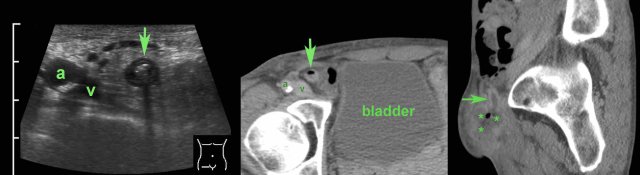

Another pitfall is tip-appendicitis, where the inflammation is confined to the distal tip.

If only the normal, proximal part (arrows in A) is visualized, and the distal end (arrows in B) would have been obscured by bowel gas, a false-negative diagnosis may be the result. (a and v = iliac artery and vein)